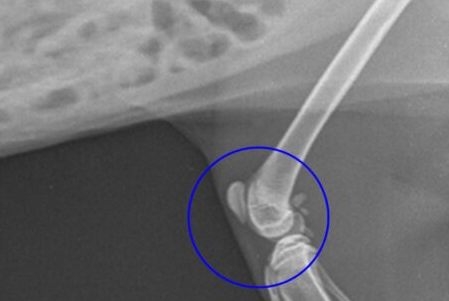

슬개골 탈구는 무릎 관절을 구성하는 슬개골(무릎뼈)이 제 위치에서 벗어나는 질환으로, 진행 단계에 따라 증상이 점차 심해지며 우리 아이의 삶의 질을 크게 떨어뜨릴 수 있습니다.

슬개골이 항상 빠져 있는 상태가 되며, 손으로 밀어 넣으면 일시적으로 제자리로 돌아오지만 곧 다시 탈구되는 단계입니다. 이 단계부터는 관절염이 동반되는 경우가 흔합니다.

가장 심각한 단계로, 슬개골이 완전히 탈구되어 손으로 밀어도 제자리로 돌아가지 않는 상태입니다. 이 단계에서는 심각한 관절 변형이 발생합니다.

- 증상 특징: 슬개골이 영구적으로 탈구되어 있으며, 무릎 관절 구조 자체가 심하게 변형됩니다.

- 다리 변형: 양쪽 뒷다리가 심한 O자 또는 X자 형태로 변형되거나, 무릎이 펴지지 않고 구부러진 상태로 굳어질 수 있습니다.